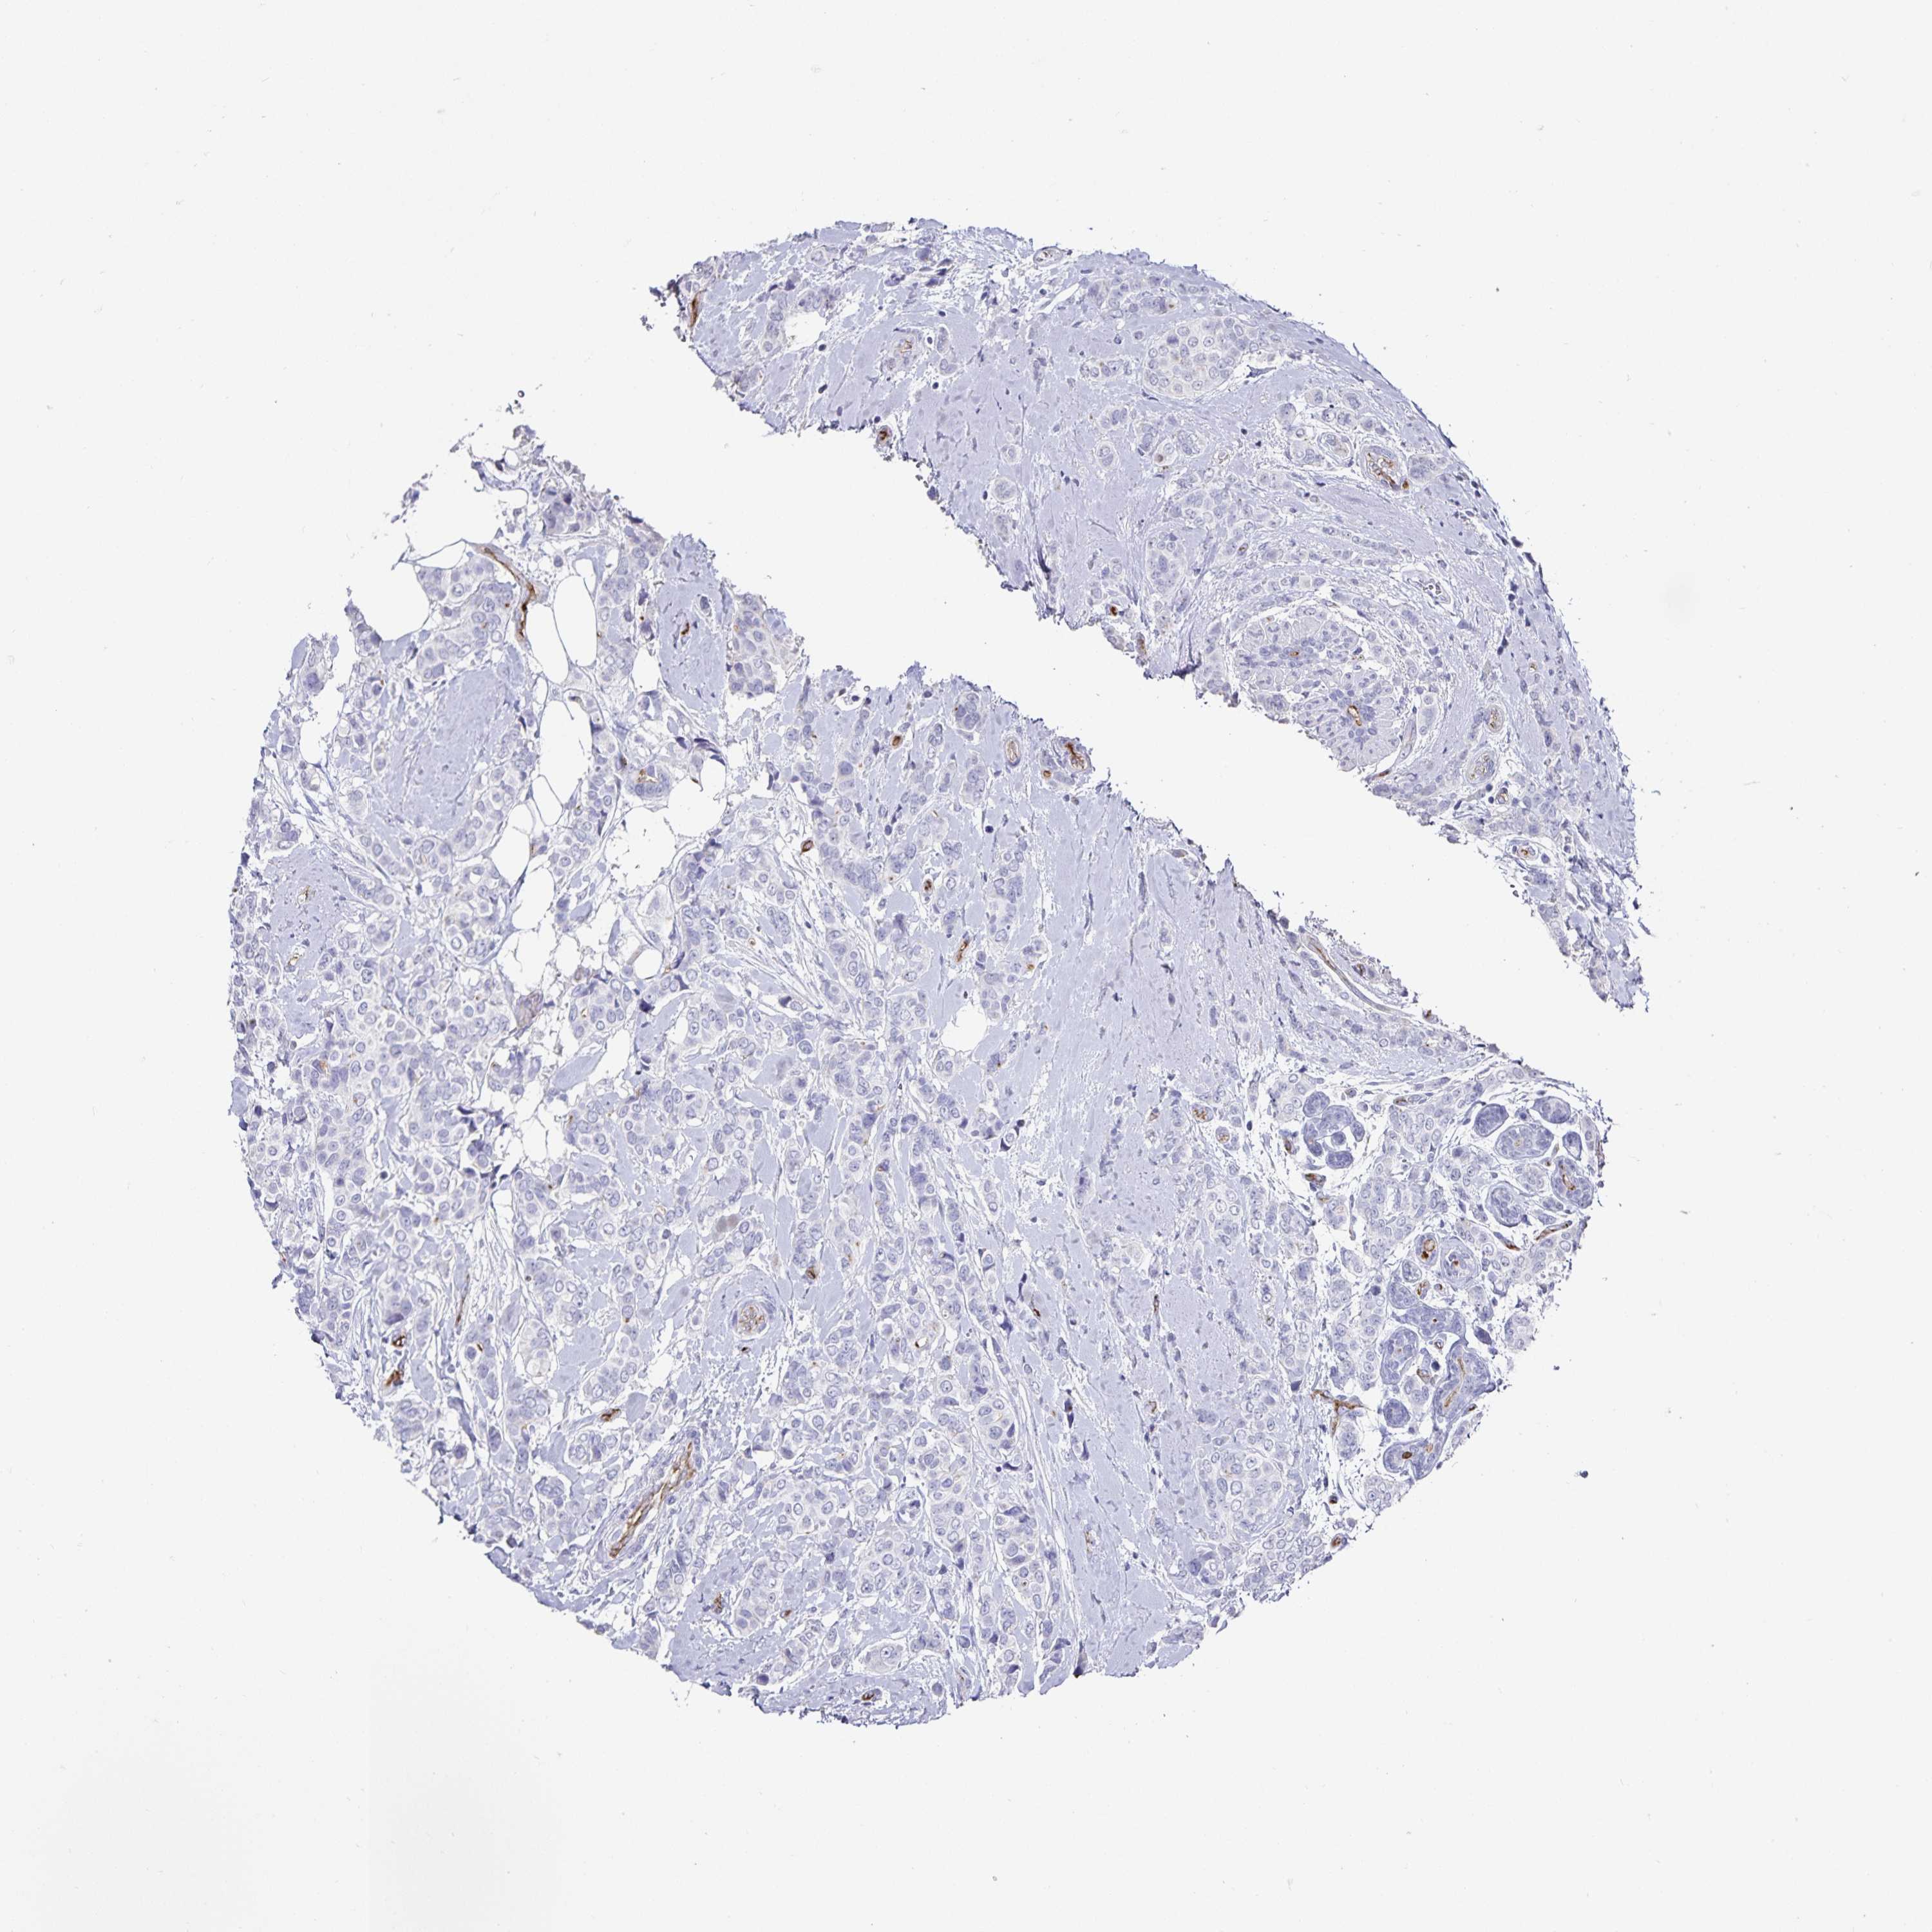

CANCER BREAST CANCER Show tissue menu

BRCA TCGA BRCA VALIDATION PROTEIN EXPRESSION